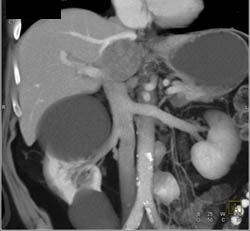

Diagnosis

Cystadenoma